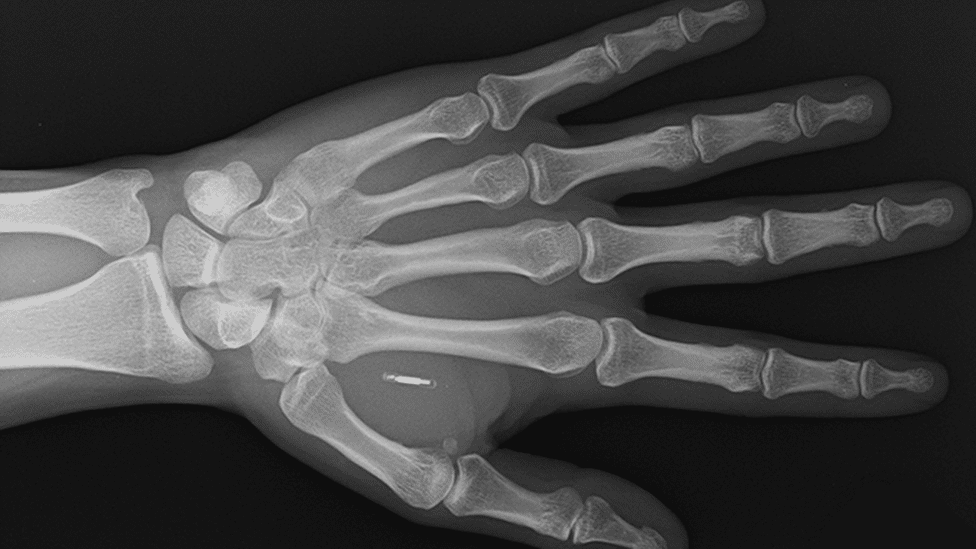

On može da plaća rukom zato što mu je 2019. godine ispod kože ubrizgan beskontaktni mikročip za plaćanje nešto veći od zrnca pirinča.

Voletmorov implantat, koji teži manje od grama, sastoji se od sićušnog mikročipa i antene obložene biopolimerom – materijalom prirodnog porekla sličnom plastici.

U Holandiji, Paumanov čip za plaćanje ima ugrađeno LED svetlo sa kinetičkim izvorom napajanja preko kretanja njegovog tela.